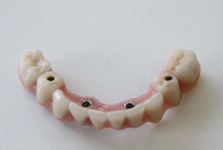

Protetické řešení může být pomocí můstku, který je kotvený na implantátech nebo pomocí jednotlivých korunek na implantátech.

V zásadě je možné do těchto můstků zařadit i přirozené zuby, zejména pokud je potřeba tyto zuby ošetřit proteticky – korunkami. Korunky nebo můstky mohou být na implantáty nacementovány nebo přišroubovány.

Pevné můstky – lepené nebo šroubované

Třmeny

Kulové attachmenty

Sub-Tec Locator®

S pomocí zubních implantátů můžeme díky různým kotevním systémům (třmeny, kulové hlavy, Locatory) zajistit stabilitu a držení protézy nebo při použití většího počtu implantátů zhotovit pevné náhrady – můstky nalepené nebo našroubované na pevno na implantáty.